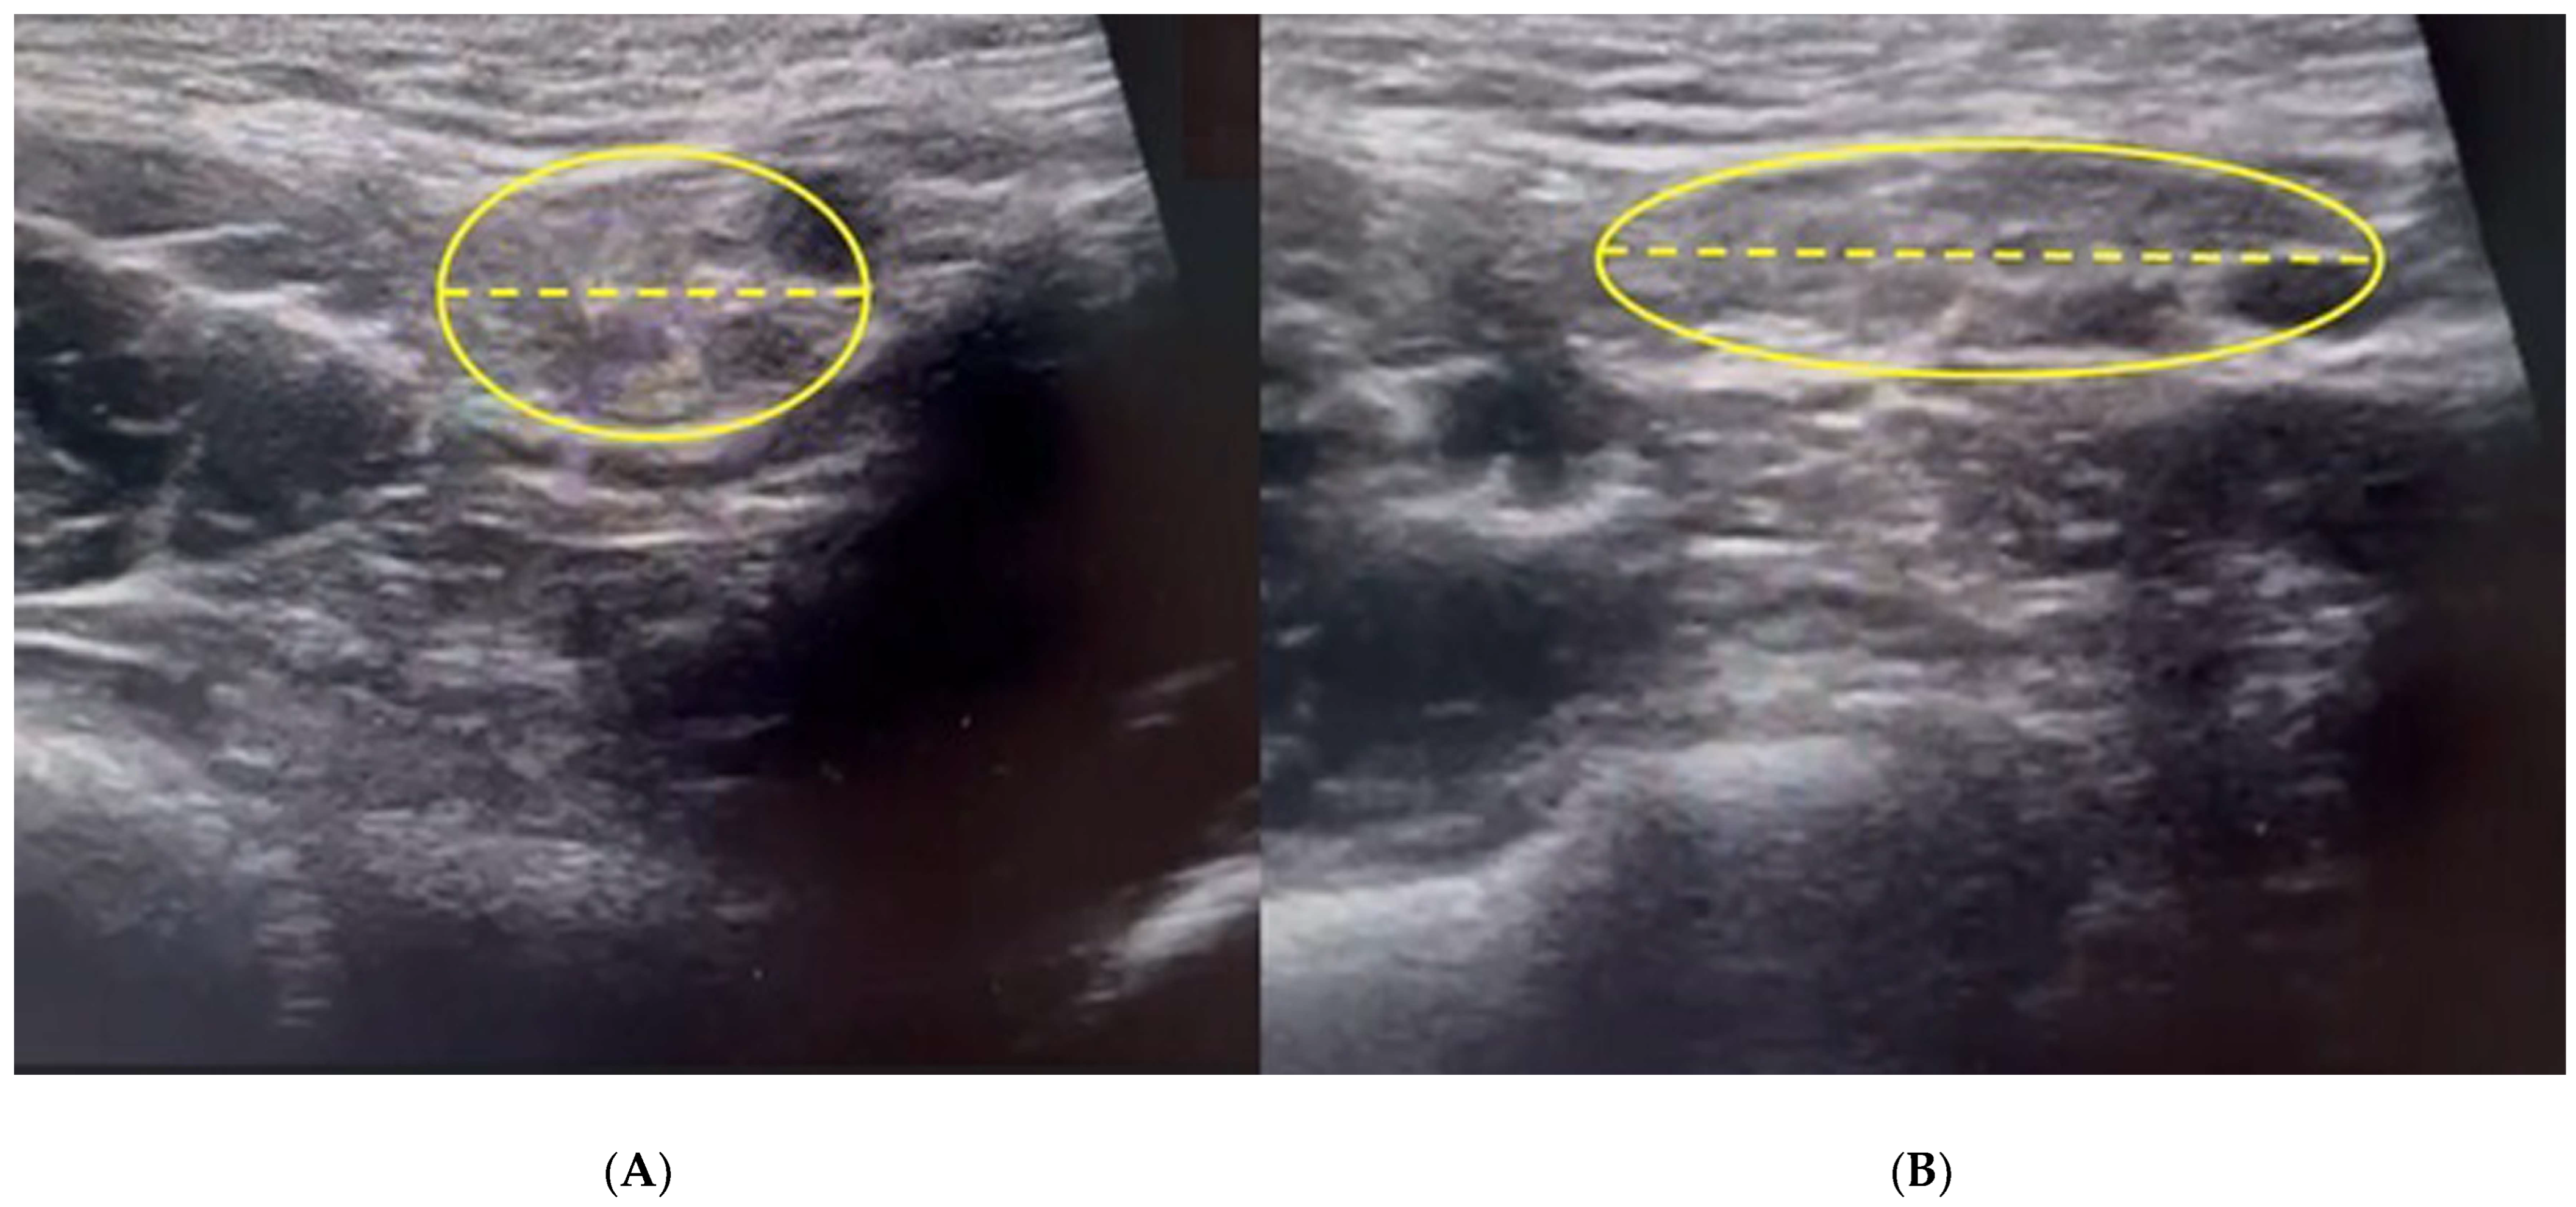

3.2. Dynamic Ultrasonography Examination

- Vasileff, W.K.; Nekhline, M.; Kolowich, P.A.; Talpos, G.B.; Eyler, W.R.; van Holsbeeck, M. Inguinal Hernia in Athletes: Role of Dynamic Ultrasound. Sports Health 2017, 9, 414–421. [Google Scholar] [CrossRef] [PubMed] [PubMed Central]